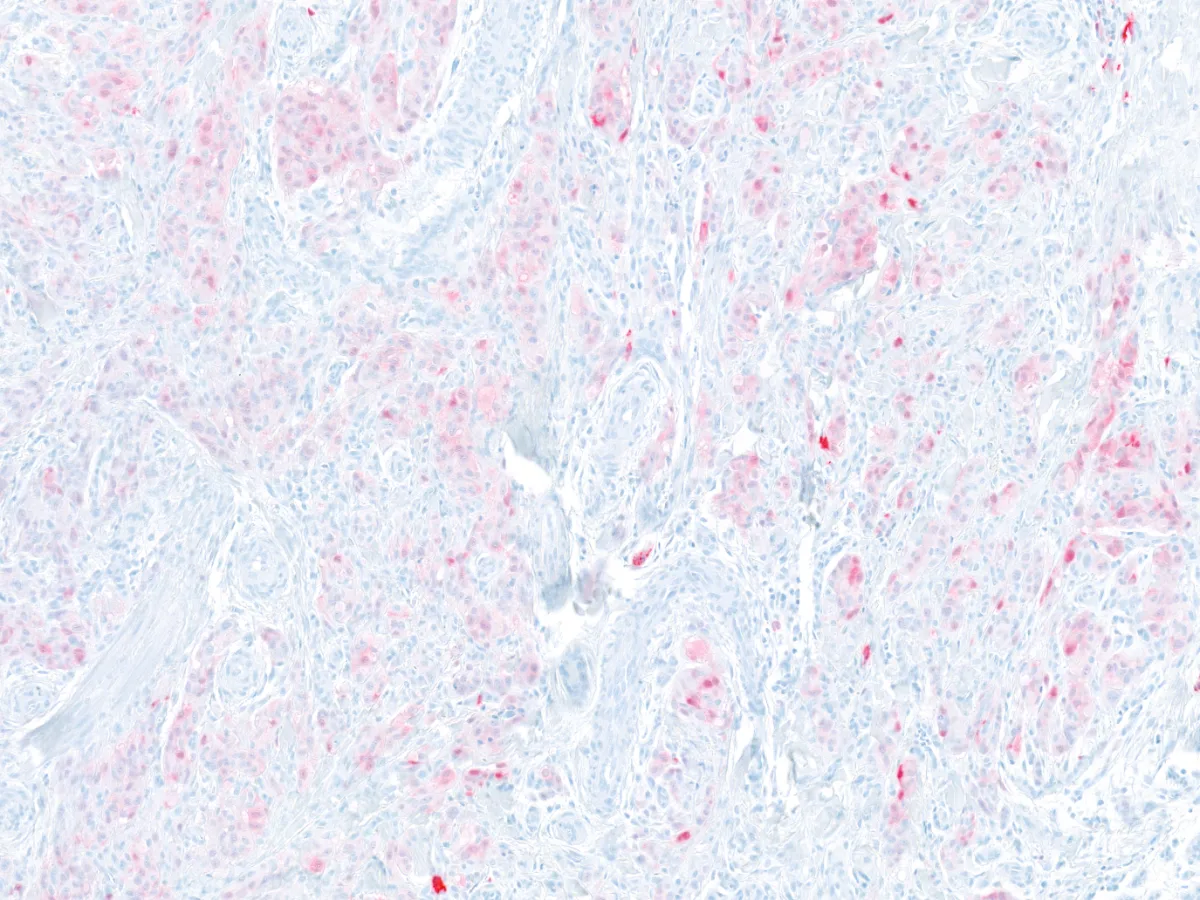

6. Ki67-MART1 40x

- Todos los tumores expresan SOX10. En un 50% de los casos expresan S100 con patrón difuso. Melan-A/MART-1 y HMB-45 se expresan focalmente. La inmunohistoquímica para TRIM11 es típicamente positiva nuclear en la periferia del tumor. Pueden expresan Pan-TRK (57% citoplasmático difuso, 36% citoplasmático parcheado), a pesar de no tener mutaciones de TRK. PMID: 35993578; PMID: 29240581.